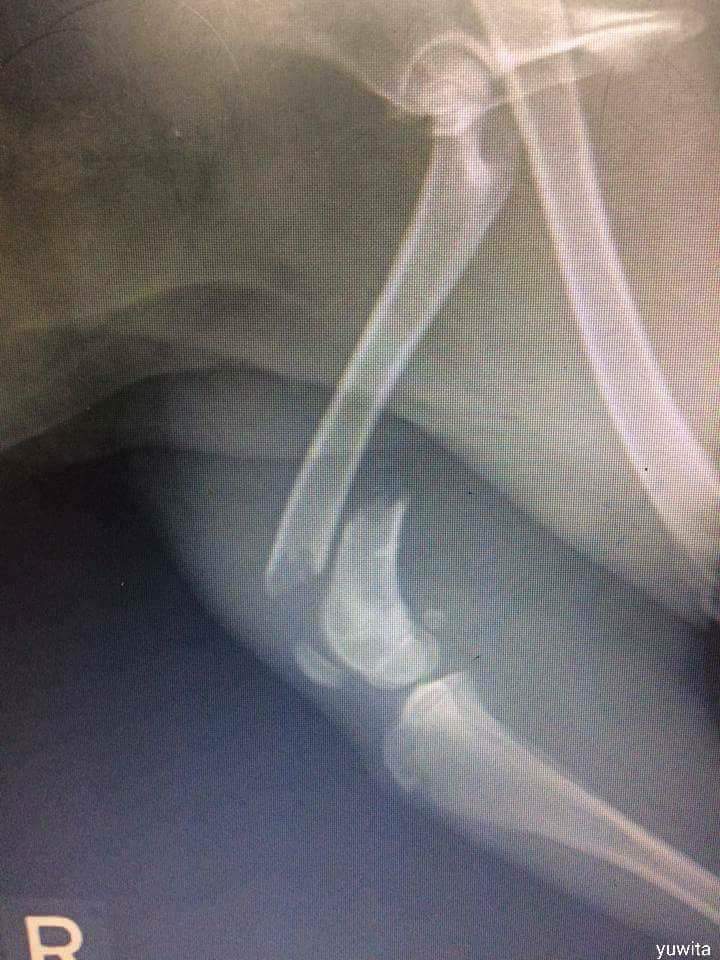

ผลการเอกซ์เรย์คือกระดูกแตก ต้องเสียค่าใช้จ่ายประมาณ 1,500 เหรียญ (ราว 12,00 บาท) เธอก็จัดแจงออกประกาศเรี่ยไร ซึ่งก็มีผู้บริจาคให้แล้ว 1,100 เหรียญ